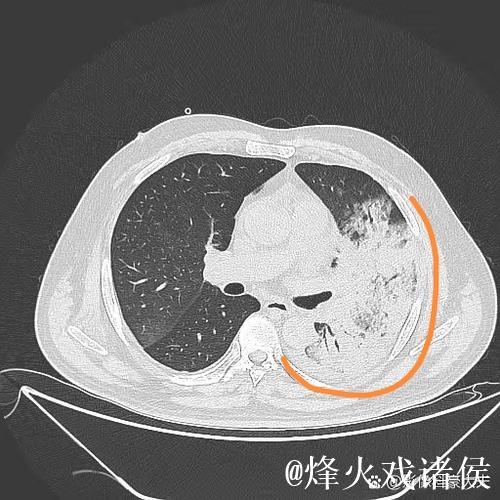

肺炎之所以让人恐惧,不仅因为它可能引发呼吸衰竭,甚至威胁生命,更因为它在短时间内剥夺了一个人对自己身体的信心。高烧、胸闷、呼吸困难,让人感到前所未有的无助。埃迪豪在住院期间,体验到那种“自己什么也做不了,只能依赖他人”的状态,这种深度依赖,让他对医护人员的信任不再停留在口头上,而是带着一种带有生死重量的感激。在无数次被抽血、做影像检查、调整药物方案的过程中,他感受到的是一种系统性的支撑机制从分诊、检查到治疗,再到随访,每一个环节都需要专业、协作和责任心。正是这种连贯的医护流程,让肺炎这样的急性疾病可以被及时识别和有效控制。

想象这样一个并不夸张的场景某个冬天的深夜,一位普通中年人因为持续高烧、咳嗽不止被家人紧急送往医院急诊。起初他以为只是普通感冒拖一拖就好,但胸闷和呼吸急促让他开始害怕。急诊医生为他安排了血常规、胸部影像检查,很快诊断出是肺炎并且已经出现肺部大片感染。值班的护士迅速为他建立静脉通路,挂上抗感染和补液的药物;呼吸科医生查看片子后,决定将他收入病房,密切监测血氧和生命体征。几天后,随着体温逐渐下降、咳嗽好转,他终于能平稳入睡。出院时,他握着主管医生的手说的一句“谢谢你们救了我”,背后是一整套完备的医疗体系在运转。这种经历,也正是很多人在重病之后才真正理解的现实只有当你真正被送进急诊室,才会明白一个反应迅速、配置合理、运行有序的医疗体系有多重要;只有当你在凌晨三点看到仍在查房的医生和整理病房的护士,才会明白医护人员的责任感远比外界想象更为沉重。